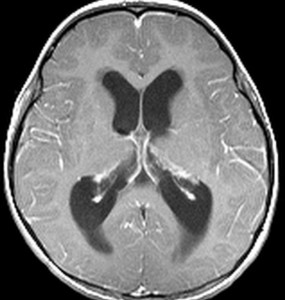

左は正常な子どもの脳室です。右は第4脳室腫瘍のために軽度の水頭症になった子どもの脳室です。髄液が溜まって側脳室が拡大していますが,このくらいだと緊急に手術をする必要はありません。